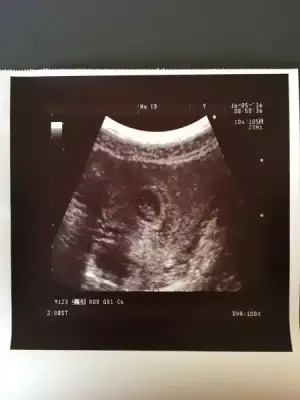

kızlar benim de 5 haftalık bir ultrason görüntüsü var tam ortada demişti dr.um .

bu hafta sonu 7. hafta kontrolüm var , ctesi yi iple çekiyorum , benimkini de yorumlarsanız sevinirim

bu hafta sonu 7. hafta kontrolüm var , ctesi yi iple çekiyorum , benimkini de yorumlarsanız sevinirim